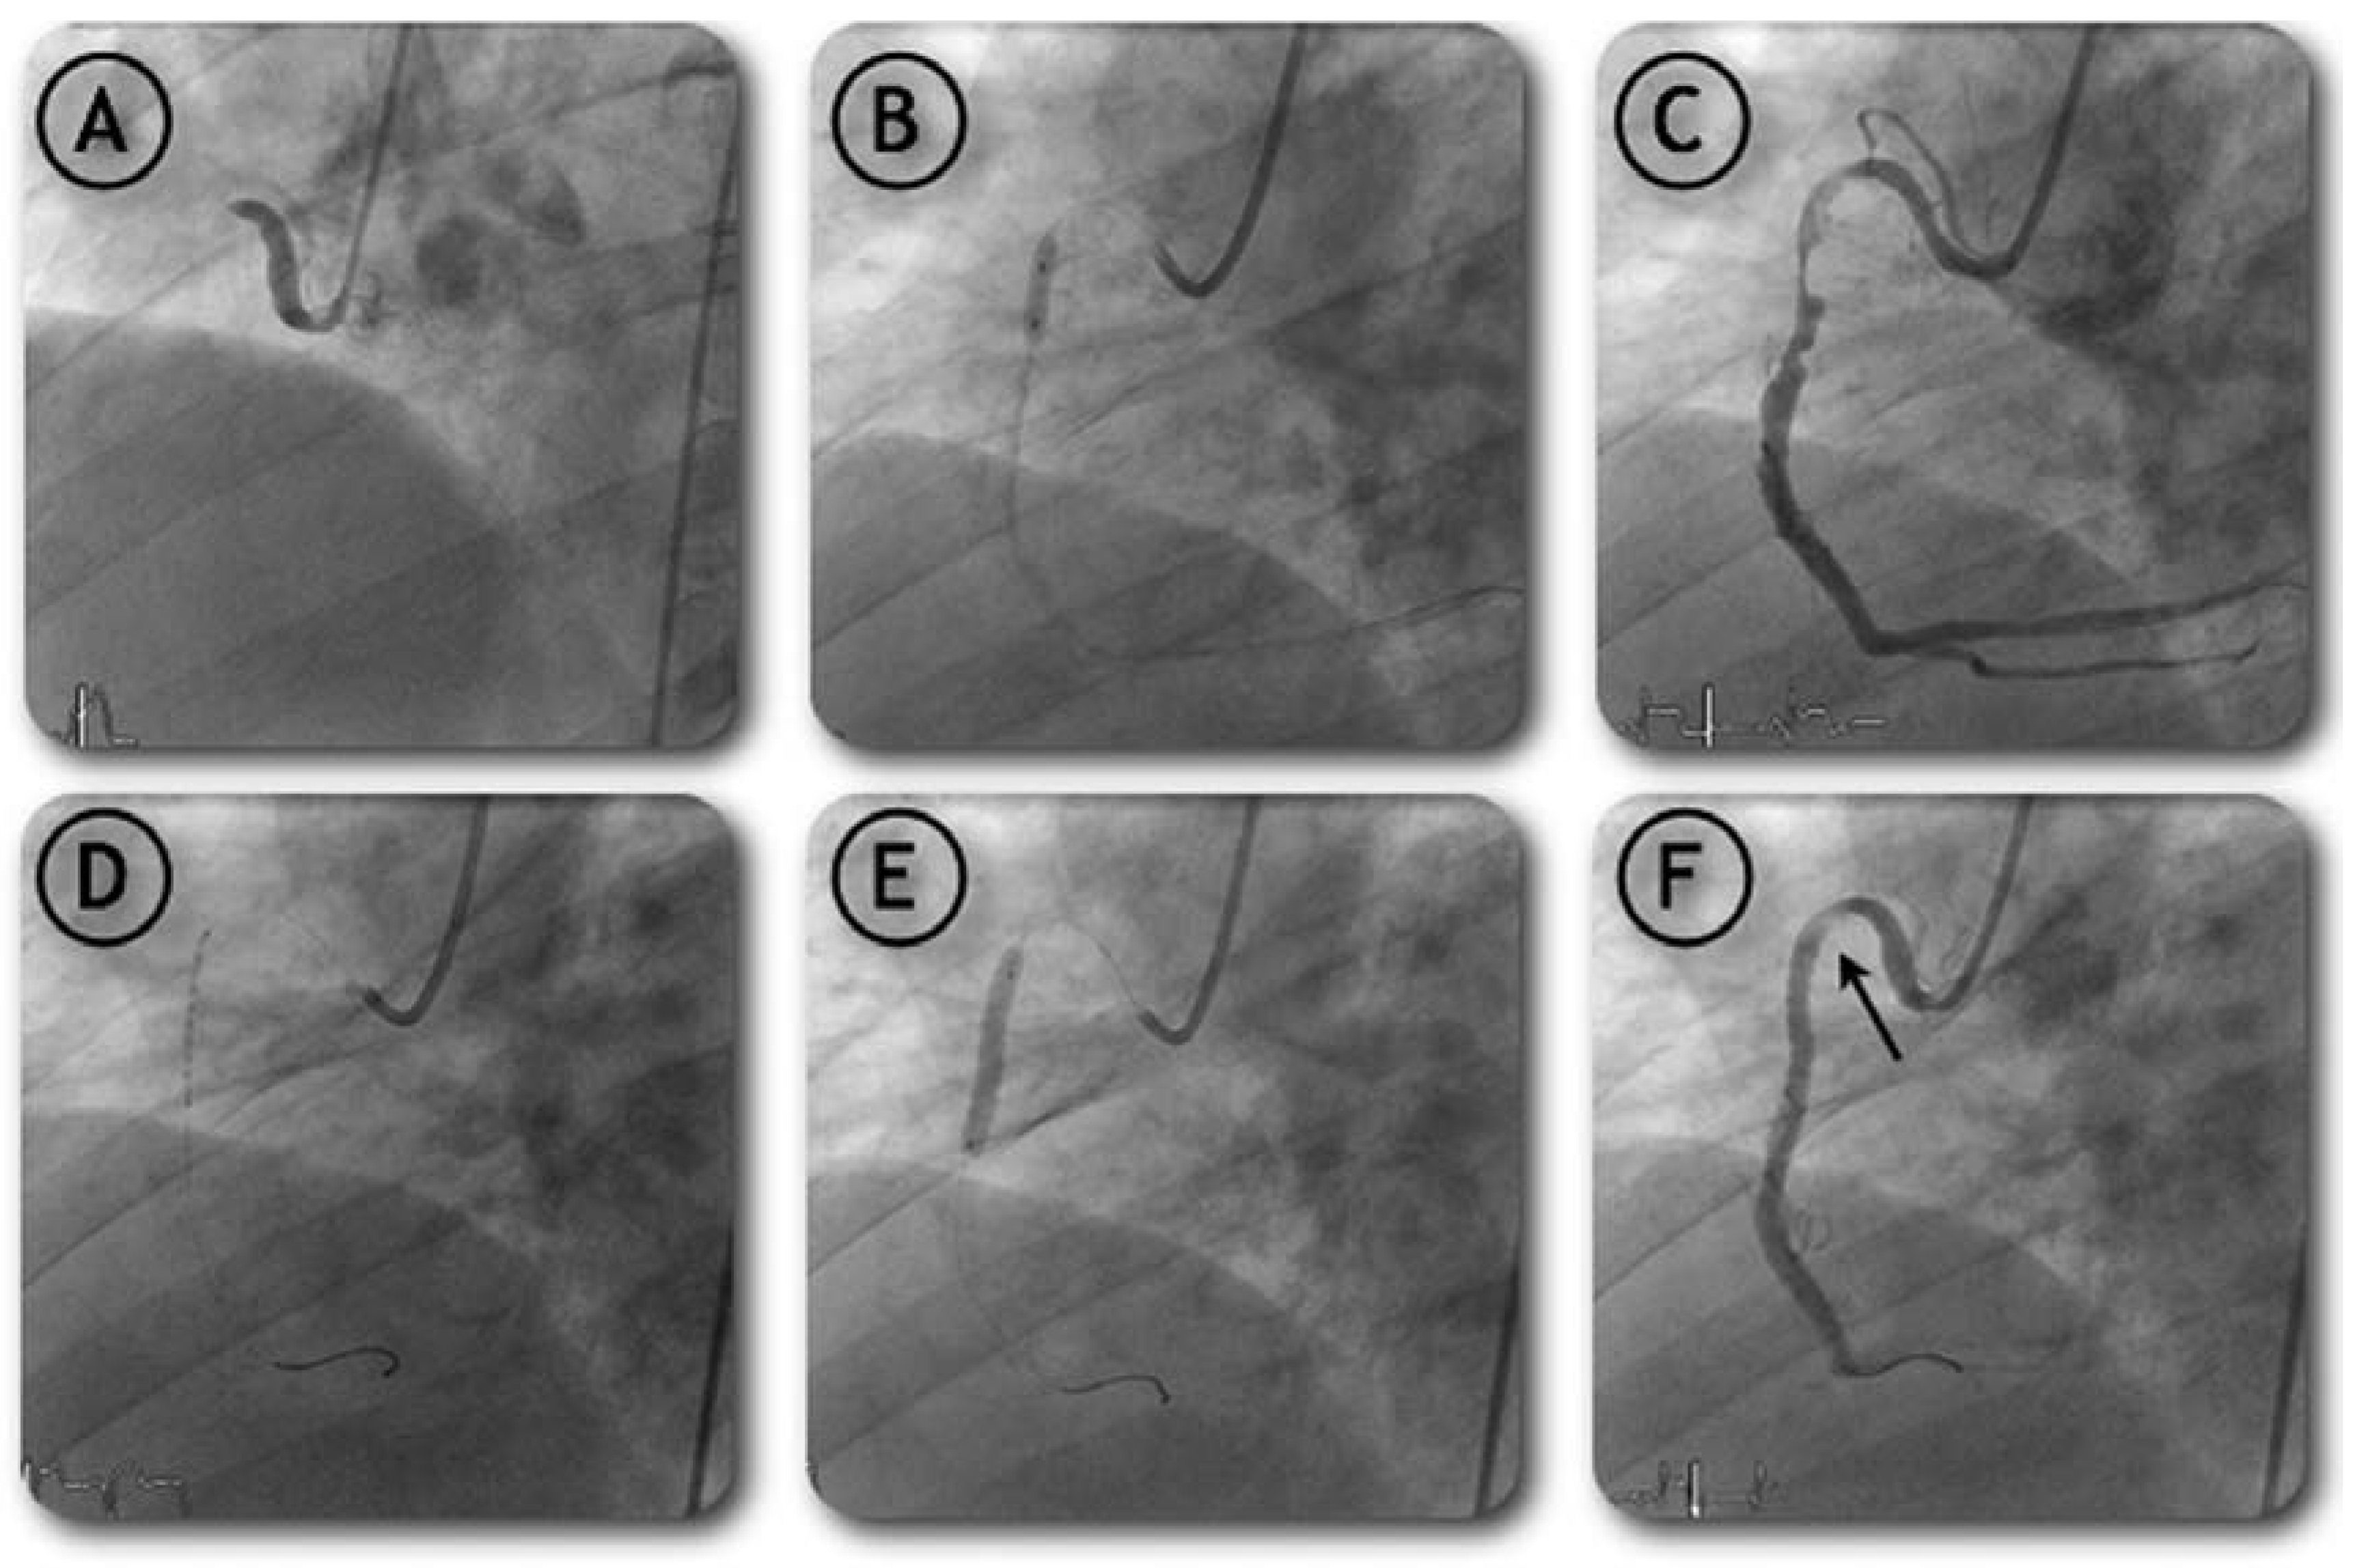

Variation on the Anchor Balloon Technique for Difficult Stent Delivery

Case report